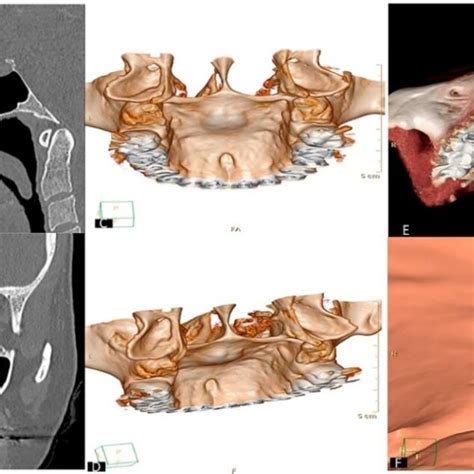

- Pruebas radiográficas: Aunque no es común ni necesario en todos los casos, es posible que para dar un diagnóstico acertado y completo, el médico solicite pruebas complementarias de imágenes, como radiografías o tomografías. Así puede verificar el tamaño, forma o diferenciar si se trata de hueso o tumores.

- Diagnóstico diferencial: Para distinguir entre un osteoma o tumor benigno osteogénico, se puede tomar una radiografía, además de que son lesiones de crecimiento lento, que continúan aumentando de tamaño aún después de la pubertad. Los quistes se diferencian debido a que se forman en tejidos blandos o glándulas. Y por último, los tumores malignos no son comunes en la zona donde aparecen los torus y presentan dolor, crecimiento rápido y otros síntomas.